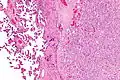

| Micrograph of a chorangioma (right of image). H&E stain. | |

Histologically, chorangioma consist of abundant vascular channels and may be cellular.

Micrograph of a chorangioma (right of image) and normal placenta (left of image). H&E stain.